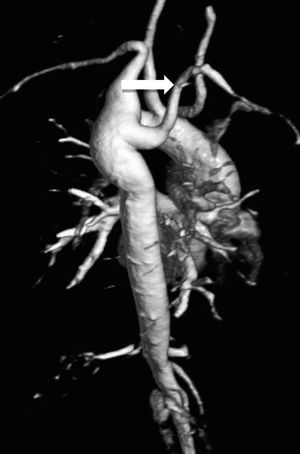

B. Aortic abnormalitiesB.1. Coarctation of the aortaCoarctation of the aorta (CoA) affects around 12% of women with TS11 and is usually diagnosed in infancy, often with congestive heart failure in critical cases17 (Figure 3).

Coarctation of the aorta (white arrow) in a 24-year-old TS woman in different projections: (a) sagittal-oblique cine magnetic resonance image, (b) volume-rendered magnetic resonance aortography (posterior-oblique view), (c) magnetic resonance aortography maximum intensity projection (sagittal-oblique view).

Indeed, in contrast to BAV, which is detected by screening, CoA is usually diagnosed based on clinical grounds – HTN and brachial-femoral delay are common features. However, since many cases are detected later in life, any woman with suspected CoA should have a CMR or computed tomography (CT) angiography with three-dimensional reconstruction of the thoracic aorta.1,11